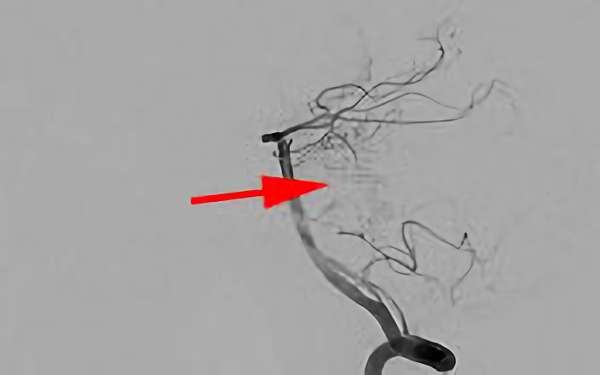

No.1620 手術前

No.1620 手術中

No.1620 手術後